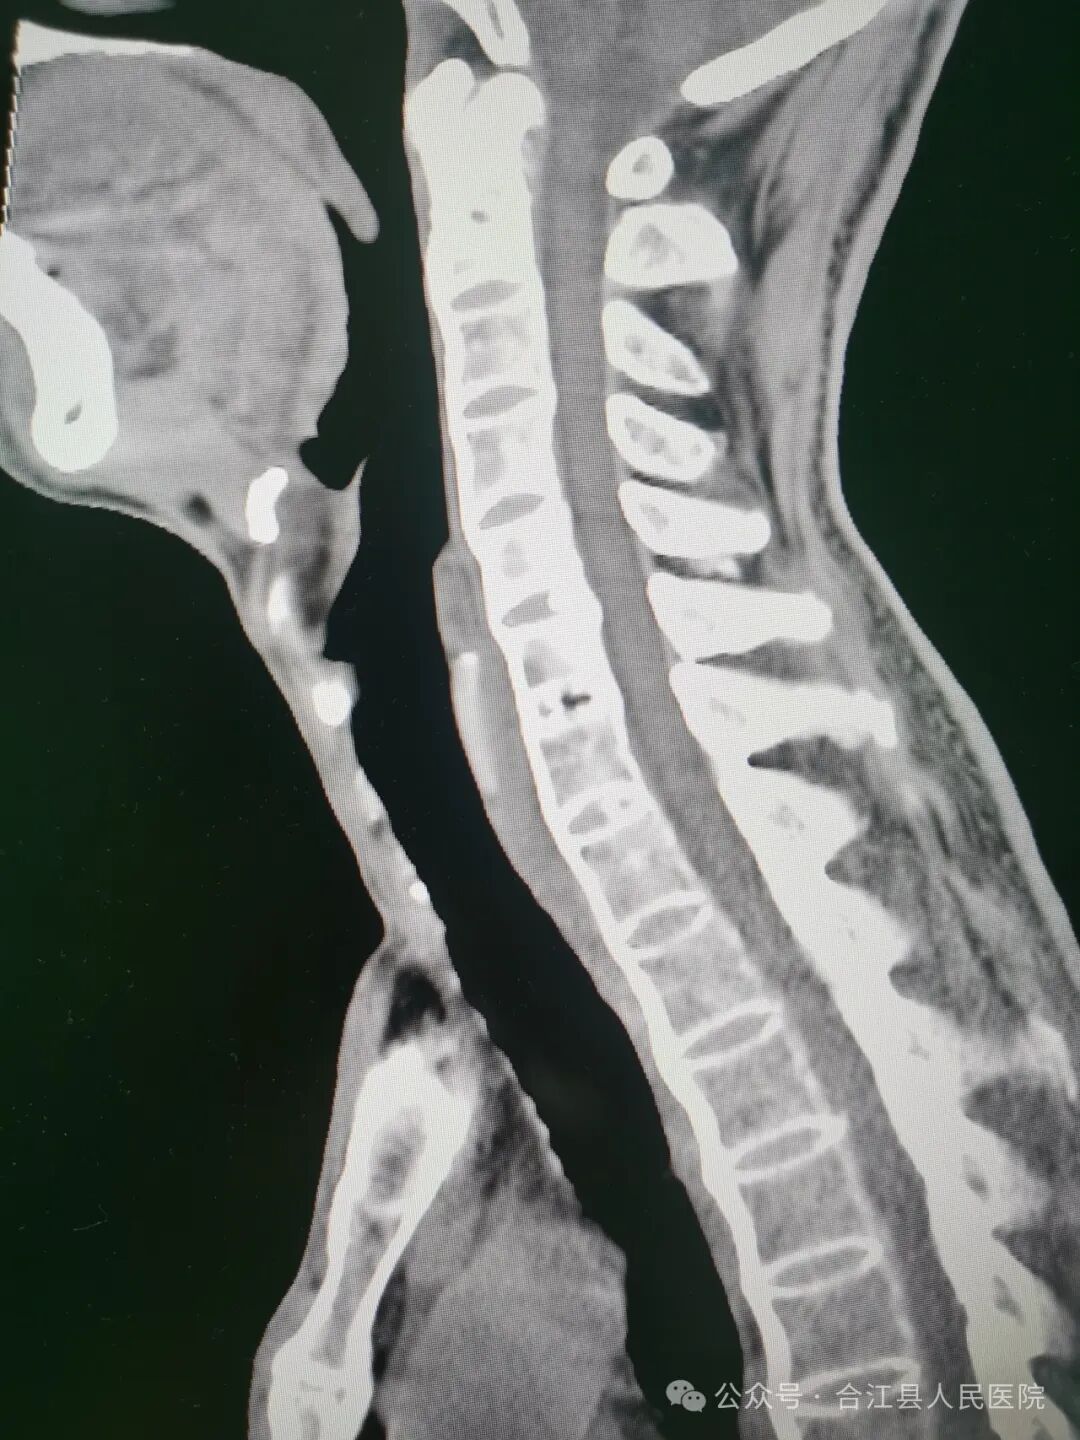

经创伤外科和麻醉科详细病史采集和查体,徐先生确实不是普通气道,气道处理非常棘手。颈椎、腰椎曲度变直,椎体“竹节样改变”。